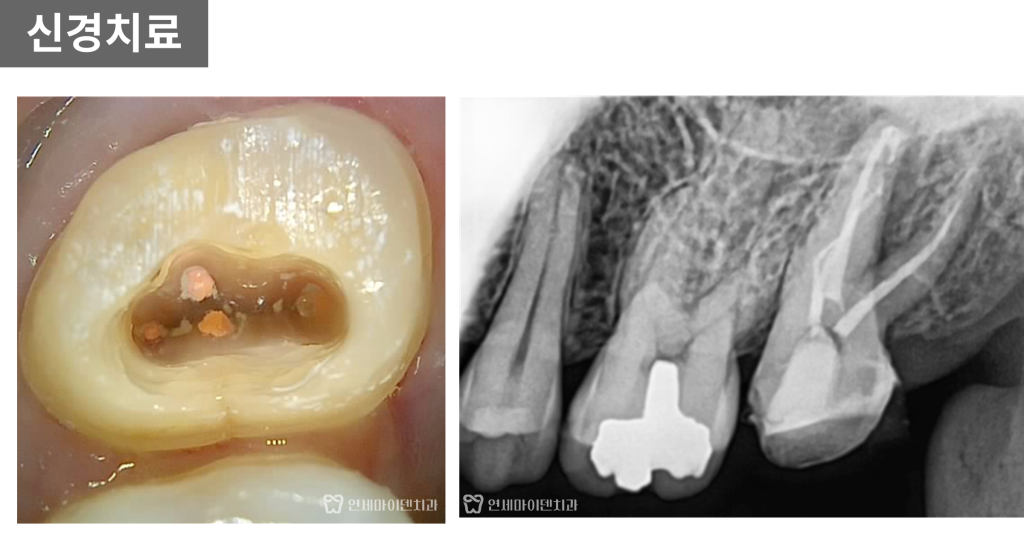

초기 검사에서 엑스레이상

충치나 뚜렷한 염증은 보이지 않았고,

잇몸 상태 역시 비교적 안정적인 모습이었습니다.

육안으로 확인했을 때도

표면이 약간 거칠어 보이는 것 외에는

특별한 이상이 없는 상태였습니다.

큐레이 검사를 통해

치아 표면에 미세한 금이 간 라인이

명확하게 확인되었습니다.

실제로 보철물을 제거하고

내부를 확인해보니

통증의 원인은 크랙이 맞았습니다.

추가 엑스레이에서

치아 주변 뼈가 녹아 있는 소견이 나타났습니다.

초기 내원 당시에는 없던 변화였지만

불과 2~3주 사이에 급격하게 진행된 상태였습니다.